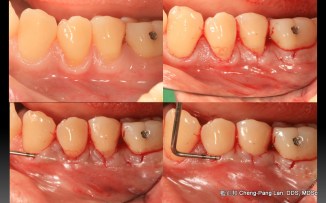

Root Coverage – Coronally Advcanced Flap with Connective Tissue Graft- Case B

Recipient Site: Harris’s technique, 1992